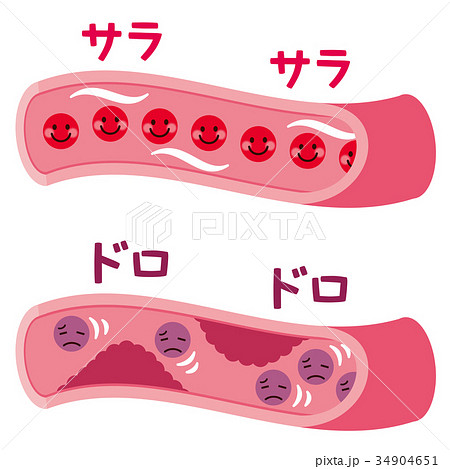

正常な血管と血栓ができた血管 イラスト素材5358451- フォトライブラリ。

血栓ができている血管 イラスト素材6665451- フォトライブラリ。